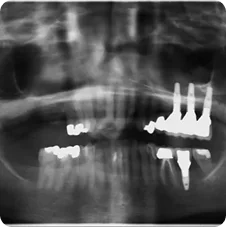

Case #1 was done with the coordination of Dr. Brian Assael D.D.S. Berkeley, CA. www.berkeleydds.com

Pre-operative

Post-operative Implant Placements